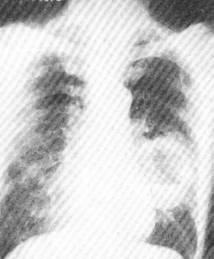

支气管肺癌 (1)x线检查:正侧位胸片可见有:①肺门包块影或肺内孤立结节状病灶,肿块边缘毛糙,有时呈分叶状。②肺部炎症样浸润阴影。③弥漫型结节状影。④癌性空洞,其特点为洞壁厚、内壁不整,呈偏心性无液平面。⑤间接征象有局限性肺气肿,阻塞性肺炎, 肺不张,肋骨破坏,胸腔积液等。支气管断层摄影可了解包块位置、大小及有无支气管受压或狭窄。选择性局部支气管造影,可显示支气管受阻、移位或聚拢情况有助诊断。 医学百科网 | YxBaike.Com